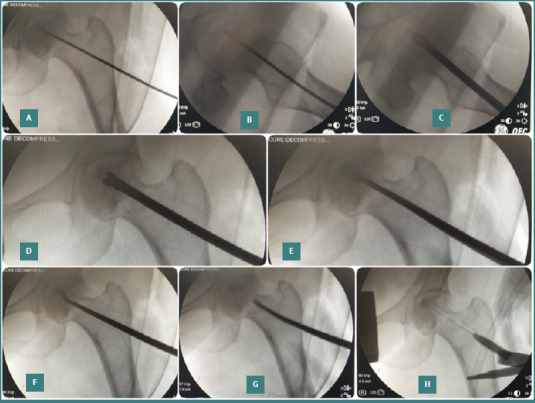

Osteonecrosis of the femoral head (ONFH) is a challenging condition that mainly affects young and middle-aged adults, causing pain, disability, and joint collapse. Current treatment options include medications, physical therapy, and surgical interventions such as core decompression and total hip replacement. However, there is growing interest in regenerative medicine for managing ONFH. This study evaluated the outcomes of core decompression augmented with adult autologous live cultured osteoblasts (AALCO) in patients with early-stage ONFH. Patients diagnosed with ONFH, Ficat-Arlet Grades 1, 2, and 3, underwent a staged procedure involving bone marrow aspiration and the cultivation of 48 million osteoblastic lineage cells. Subsequently, this culture was injected following core decompression and curettage of the necrotic area in the femoral heads. Patients were then followed for 18 to 26 months and evaluated for radiological progression of the disease and changes in functional outcome using the Harris Hip Score (HHS) and Visual Analog Scale (VAS). Forty-eight hips (34 patients with 14 bilateral ONFH) were included in the study and followed up for 18 to 26 months. During this period, 29 patients (40 hips) exhibited progressive signs of healing, resulting in a significant improvement in the mean HHS and a reduction in VAS scores. Core decompression augmented with implantation of autologous live cultured osteoblasts is a reliable treatment approach for managing the early stages of ONFH in young patients caused by various factors. The method aims to halt disease progression through osteoblastic stem cell-mediated new bone formation, leading to improved functional outcomes and potentially delaying or avoiding the need for total hip arthroplasty.